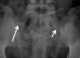

Short rib syndrome type 3

Short rib–polydactyly syndrome is a family of four closely related dysplasias: [Source: Wikipedia ]